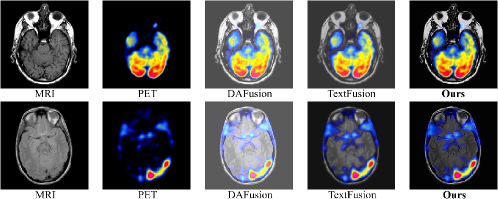

Refer to caption

Figure 13: Qualitative results of image fusion on the Harvard Medical dataset.

TABLE XI: Quantitative results of image fusion on the Harvard Medical dataset. (Optimal: bold; 2nd-best: underlined; mRank denotes the average rank across all evaluation metrics).

Method mRank\downarrow Qabf\uparrow SSIM\uparrow VIF\uparrow SF\uparrow MI\uparrow

TextFusion 2.200 0.274 0.296 0.532 10.548 1.598

DAFusion 2.600 0.484 0.283 0.514 16.296 1.571

Ours 1.200 0.515 0.384 0.537 21.014 1.573

IV-E Generalizability

To validate the generalizability of the proposed model, a medical-image fusion task is conducted on the Harvard Medical dataset. Figure 13 compares representative qualitative MRI–PET fusion results. Relative to DAFusion and TextFusion, the proposed method preserves high contrast while revealing clearer organisational structures with sharper boundaries; for example, the cerebral cortex and metabolically active regions exhibit higher brightness and uniform distribution, edge details are sharper and artefacts are suppressed, thus providing improved diagnostic readability and structural completeness.

Quantitative results are summarised in Table XI. The proposed model attains the highest Qabf and SF scores, markedly surpassing TextFusion and DAFusion, which indicates superior contrast handling and texture representation. The model also ranks first in the overall metric mRank, demonstrating stronger capability to maintain source-image structural fidelity while enhancing key salient regions, thereby exhibiting considerable cross-domain adaptability and practical potential.